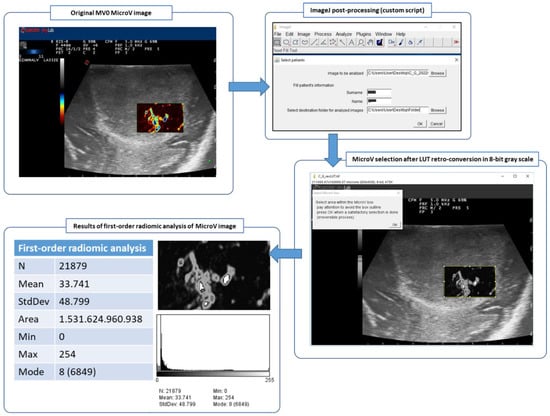

2.7.1. Post-Processing of MicroV Images

2.7.2. First-Order Radiomic Analysis

- Schindelin, J.; Rueden, C.T.; Hiner, M.C.; Eliceiri, K.W. The ImageJ Ecosystem: An Open Platform for Biomedical Image Analysis. Mol. Reprod. Dev. 2015, 82, 518–529. [Google Scholar] [CrossRef]

- Giammalva, G.R.; Viola, A.; Maugeri, R.; Giardina, K.; di Bonaventura, R.; Musso, S.; Brunasso, L.; Cepeda, S.; del Bene, M.; della Pepa, G.M.; et al. MicroV IOUS Custom MV0 LUT and Scripts for Analysis of Radiomic Features in ImageJ. Zenodo 2022. [Google Scholar] [CrossRef]